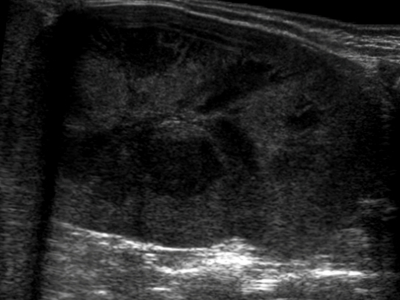

MCDK

Multicystic Dysplastic Kidney results from a ureteral obstruction before the 8th or 9th week of fetal development. MCDK is usually diagnosed prenatally or shortly after birth if an ultrasound is ordered. The affected kidney is non functioning and is replaced by cysts of various sizes and connective tissue.

- Malformation of the kidney during fetal development

- Multiple cysts

- Contralateral UPJ obstruction is found in 3% to 12%

- Usually unilateral (bilateral form is usually fatal)